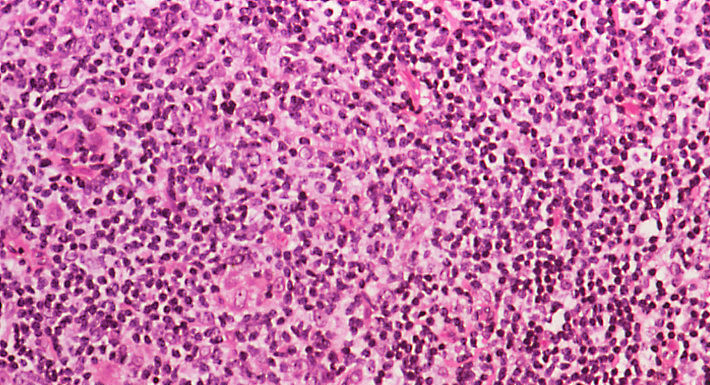

淋巴瘤的分类极为复杂,宛如一幅庞大而精细的 “拼图”,需要专业的病理学家运用先进的显微镜技术,结合特殊的组织染色方法,对肿瘤组织切片进行细致入微的观察和分析,才能逐步拼凑出其完整的面貌。从宏观层面看,淋巴瘤主要分为霍奇金淋巴瘤和非霍奇金淋巴瘤两大类型。霍奇金淋巴瘤似乎对年轻男性群体有着特殊的 “偏好”,而非霍奇金淋巴瘤则在老年人群体中更为常见。

进一步深入细分,非霍奇金淋巴瘤又可依据细胞起源的不同,分为 B 细胞淋巴瘤、T 细胞淋巴瘤和 NK 细胞淋巴瘤,这与淋巴母细胞的分化轨迹密切相关。从临床角度出发,根据肿瘤细胞的生长速度、侵袭能力以及对人体的危害程度,淋巴瘤又被划分为侵袭性淋巴瘤和惰性淋巴瘤。